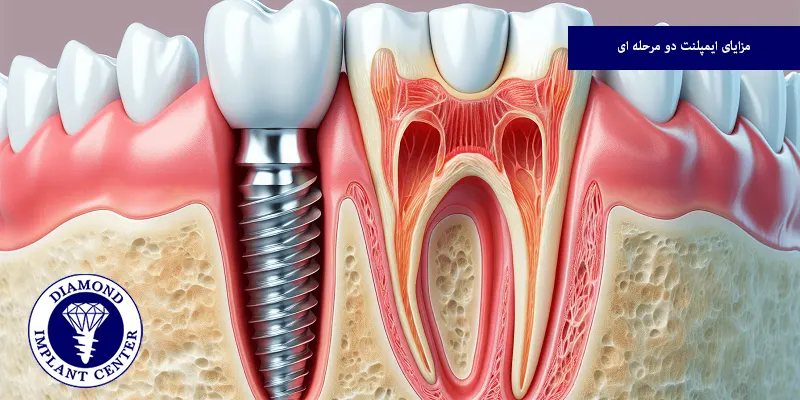

ایمپلنت دو مرحله ای چیست؟

ایمپلنت دو مرحلهای روشی تخصصی برای کاشت دندان است که در آن، روند درمان در دو فاز جداگانه انجام میشود، در مرحله اول، پایه تیتانیومی یا فیکسچر در داخل استخوان فک جای گذاری میشود تا نقش ریشه دندان را ایفا کند و سپس مدت زمانی معمولا چند ماه به استخوان فرصت داده میشود تا به طور کامل با پایه جوش بخورد و فرآیند استئواینتگریشن تکمیل شود، پس از این دوره، در مرحله دوم، جراحی کوچکی برای آشکار کردن پایه انجام میشود و سپس اباتمنت و تاج مصنوعی بر روی آن قرار میگیرد، این روش باعث استحکام بیشتر و نتیجهای طبیعیتر در مقایسه با روشهای یک مرحلهای میشود.

مزایای ایمپلنت دو مرحله ای

ایمپلنت دو مرحلهای بهعنوان یکی از روش های رایج و قابل اعتماد کاشت دندان، مزایای متعددی دارد که باعث شده بسیاری از بیماران و جراحان این روش را ترجیح دهند، مهمترین مزایای آن عبارتاند از:

استحکام و دوام بالا

با توجه به جوش خوردن کامل پایه یا فیکسچر به استخوان فک پیش از قرار گرفتن تاج، این روش استحکام فوق العادهای ایجاد میکند و دوام طولانی مدت دارد.

کاهش احتمال پس زدن ایمپلنت

فرصت کافی برای یکپارچه شدن ایمپلنت با استخوان، باعث میشود احتمال بروز مشکلاتی مانند شل شدن یا پس زدن ایمپلنت به حداقل برسد.